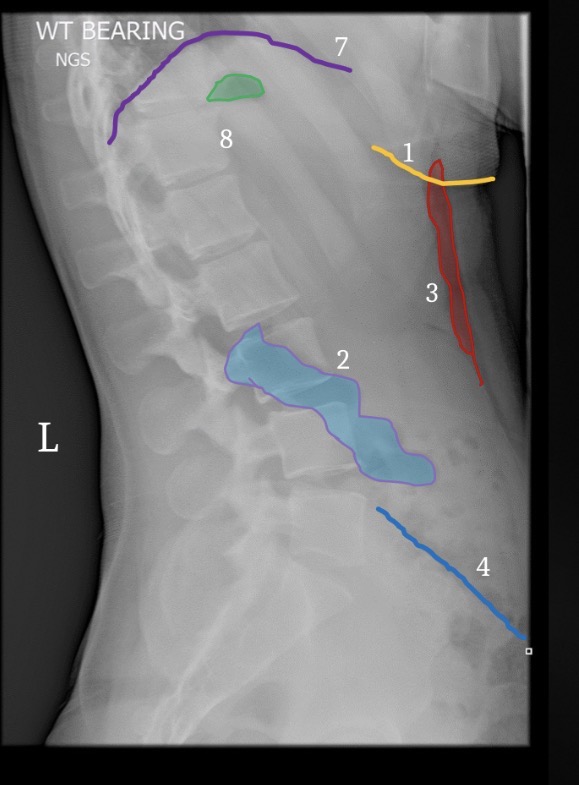

1

T12-L1 intervertebral foramen

2

Rib 12

3

Inferior articular process L2

6

Greater sciatic notch

5

Sacral canal

8

Sacral promontory

9

Iliac crest (2)

11

Transverse process L4

10

Superior articular process L5

12

Anterior body margin of L4

14

Anteriorsuperior body corner L3

15

Intervertebral disc space L1-2

Brest

Fat deep to abdominal muscle

Gluteal crease

Lateral margin left psoas muscle

7

Hemidiaphragm

Gastric air bubble